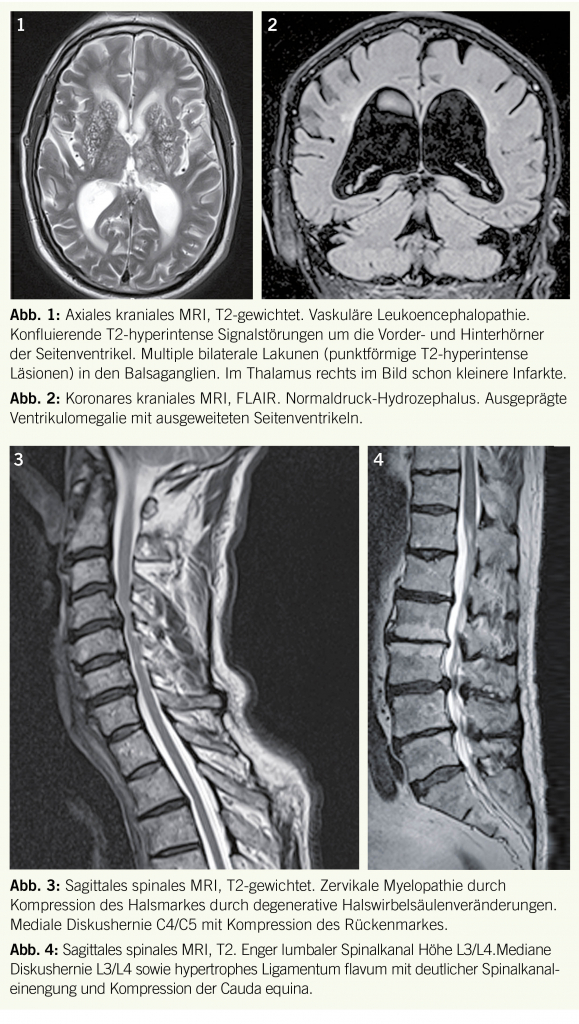

Die hemiparetische und die frontale Gangstörung als Folge eines Schlaganfalls wie auch der unsichere Gang als Folge multipler/rezidivierender Schlaganfälle ist aufgrund der akuten Präsentation und den aktuellen diagnostischen Möglichkeiten der CVI Diagnostik (kraniales MRI) meist einfach zu erkennen. Mehr Probleme kann das Erkennen der langsam progredienten Gangataxie im Rahmen einer ausgeprägteren vaskulären Leukoenzephalopathie (subkortikale arteriosklerotische Enzephalopathie, Binswanger) sein. Bei genauer Befragung finden sich doch oft akute Symptom-

episoden, die Patienten haben seit Jahren multiple vaskuläre Risikofaktoren und oft Zeichen der KHK und/oder PAVK sowie eine Urininkontinenz. Bei der Untersuchung finden sich eine (meist leichte) Spastik, Zeichen der frontalen Enthemmung, sogenannte pseudobulbäre Zeichen (Dysphagie, Dysarthrie, emotionale Labilität) und Zeichen einer demenziellen Entwicklung. Beweisend ist in den meisten Fällen die zerebrale Kernspintomographie mit einer ausgeprägten multifokalen und konfluierenden Leukoencephalopathie (Abb. 1).

Ein sehr unsicherer, sehr breitbasiger, meist auch kleinschrittiger Gang ist das wichtigste klinische Kennzeichen eines sogenannten Normaldruckhydrozephalus, eine Erkrankung des älteren Menschen (> 65 J.). Die Gangstörung ist das erste und schwerste Symptom, sie entwickelt sich schleichend und es kommt im Verlauf eine Dranginkontinenz und eine demenzielle Entwicklung dazu. Der Gang ist langsam, die Füsse kleben am Boden («magnetischer Gang») und sind oft nach aussen gedreht, es besteht eine Standunsicherheit (die Patienten halten sich fest), beim Drehen werden viele (kleine) Schritte benötigt. In der zerebralen Kernspintomographie findet man eine Ventrikulomegalie (Abb. 2). Nach spezieller Abklärung kann eine Shuntoperation die Symptome anhaltend bessern.

Auch die zervikale Myelopathie ist eine Krankheit des älteren Menschen, bedingt durch eine Rückenmarkskompression durch arthrotisch oder diskogene degenerative Veränderungen der unteren Halswirbelkörper (v.a. C5 / C6 und C6 / C7) mit konsekutiver Einengung des zervikalen Spinalkanals (Abb. 3). Anamnestisch rezidivierende Nackenschmerzen und zervikale radikuläre Beschwerden sind keineswegs obligat. Die Gangstörung ist meist das früheste Symptom, entwickelt sich aber sehr schleichend: die Patienten beklagen einen unsicheren Gang, eine Schwäche oder Müdigkeit in den Beinen, die bei längerem Gehen zunehmen kann. Die klinische Untersuchung zeigt einen unsicheren breitbasigen Gang, unsicheren oder unmöglichen Einbeinstand und eine Paraspastik mit Pyramidenzeichen der Beine.

Typischerweise nur Beschwerden in den Beinen und typischerweise belastungsabhängig (zunehmend beim Gehen) verursacht der enge lumbale Spinalkanal. Durch degenerative Veränderungen der unteren Lendenwirbelkörper (v.a. L4 / L5 und L5/S1, evtl. auch L3 / L4) (Diskusverschmälerung mit Osteophytose, hypertrophe Facettgelenkarthrose, hypertrophe Ligamenta flava, Wirbelkörpergleiten (Listhesis) und eventuell zusätzlicher Diskushernie) kommt es zur Einengung des lumbalen Spinalkanals (Abb. 4). Konsekutiv kommt es zur Kompression einzelner oder mehrerer Wurzeln der Cauda equina. Dies verursacht v.a. beim Gehen, evtl. auch beim Stehen, aber kaum im Liegen, Parästhesien der Beine und ausstrahlende (radikuläre) Schmerzen, oft bilateral. Beim Gehen bemerken die Patienten eine belastungsabhängige progrediente multiradikuläre Schwäche mit eingeschränkter Gehstrecke (Claudicatio). Diese ist bergauf weniger eingeschränkt als bergab. Beim Stehenbleiben mit Bücken oder beim Absitzen verschwinden die Beschwerden innert Minuten. Lumbago, oft seit vielen Jahren, im Stehen und Gehen ist häufig, aber keineswegs obligat. Auch hier ist die Bildgebung des lumbalen Spinalkanals (MRI) meist diagnosebestätigend. Aber aufgepasst: diese Bildgebung erfolgt im Liegen und kann daher evtl. (bei grösserer Instabilität) die tatsächliche Einengung (im Stehen) unterschätzen.